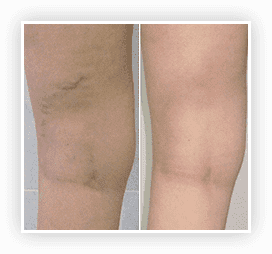

WYNIKI ZA 18 DNI

PRZED I PO Vasaxal

WYNIKI ZA 3,5 TYGODNIA

PRZED I PO Vasaxal

W wyniku zastosowania krem Vasaxal z 4% kompleksu BC uzyskano następujące dane:

Szerokość centralnego naczynia zmniejszyła się o 87,8%.

Rozszerzenie sieci naczyniowej zmniejszyło się o 90%.